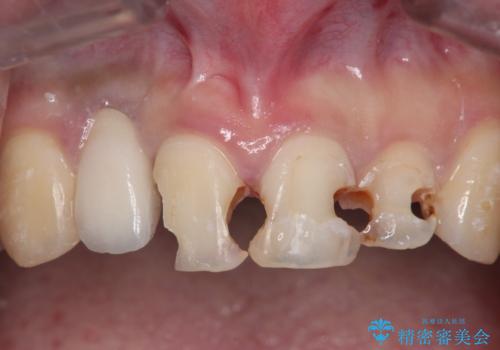

[メタルフリー治療] 金属色の見た目を改善したい

- ゴールド(金)を用いた補綴・修復が多数為されており、色調・見た目の改善を希望され来院されました。

ゴールドクラウン・インレーを除去しジルコニアオールセラミッククラウンによる再補綴治療を計画します。

ゴールドを用いたクラウン・インレーは一般的に壊れにくく・適合がよく・歯に優しいといっためりっとがありますが、数が多くなると口腔内で目立ってしまうといったデメリットがあります。